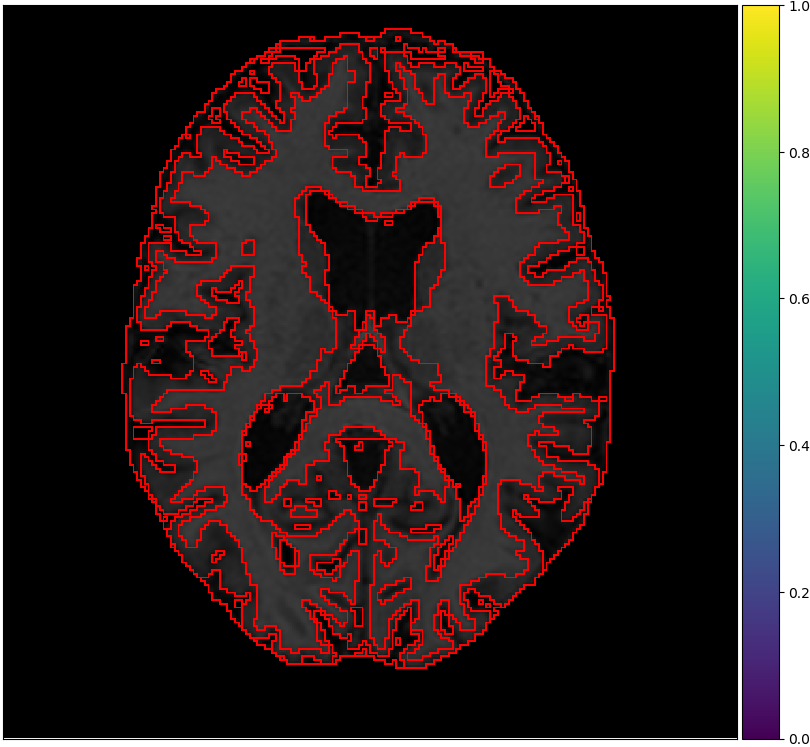

Figure 2 shows examples of each segmentation method on the MRBrainS13 data set, with Brainweb1.5T as the source center. For the unsupervised models we only show boundaries between clusters, to indicate that interpretation remains a necessary step. A couple of observations can be made: firstly, the hidden Potts models produce smoother segmentations. Secondly, the U-net over-predicts white matter in the whole image. Thirdly, the 1-nearest-neighbours classifier over-predicts background voxels in fluid regions. Lastly, all methods favour white matter over gray matter in ambiguous regions.